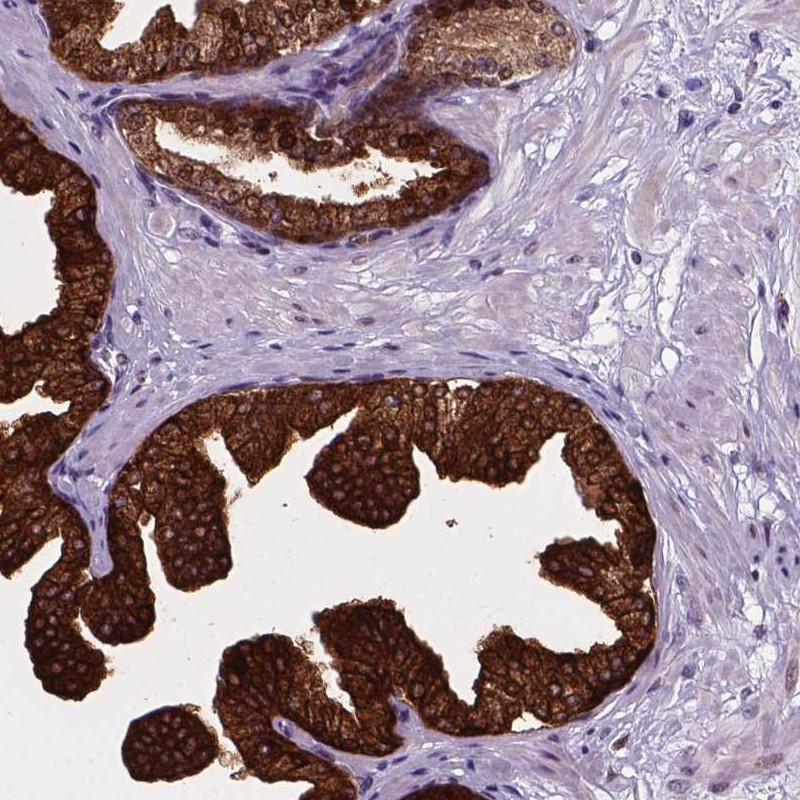

Immunohistochemical staining of human prostate shows strong cytoplasmic, membranous and nuclear positivity in glandular cells.